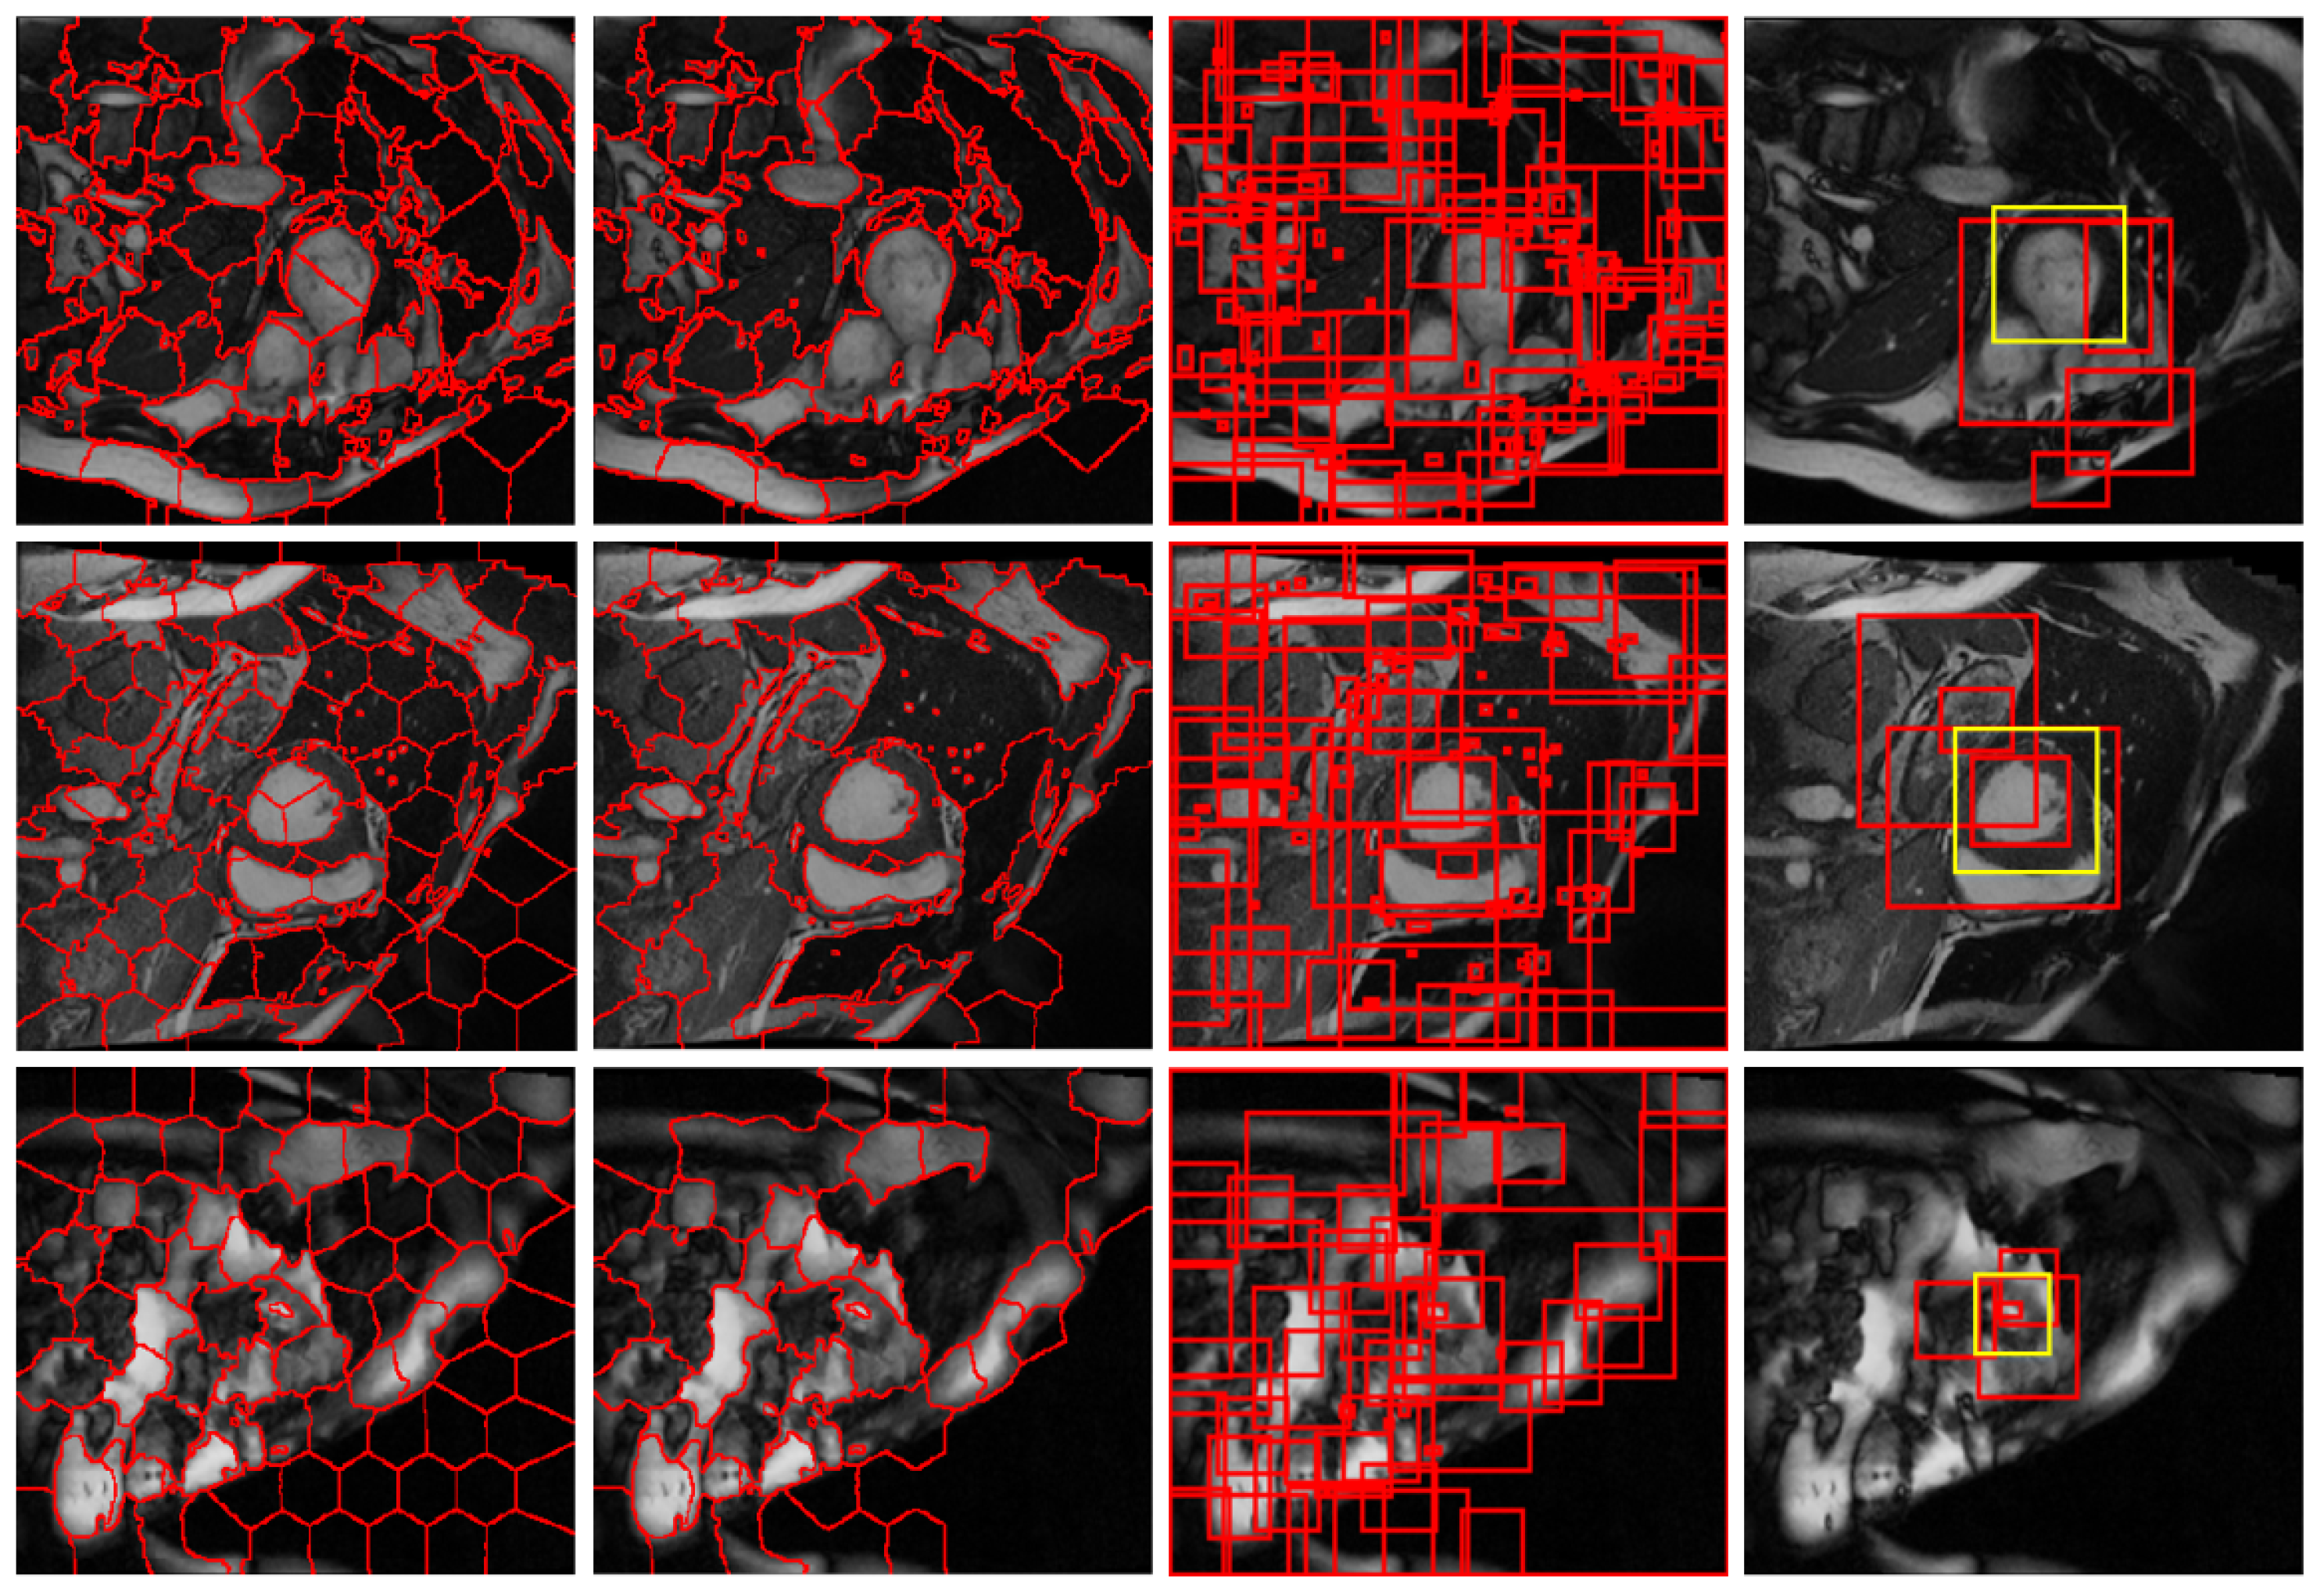

2.2.1. Structural Similarity-Enhanced Supervoxel Over-Segmentation

2.2.2. Supervoxel Region Merging by Hierarchical Clustering